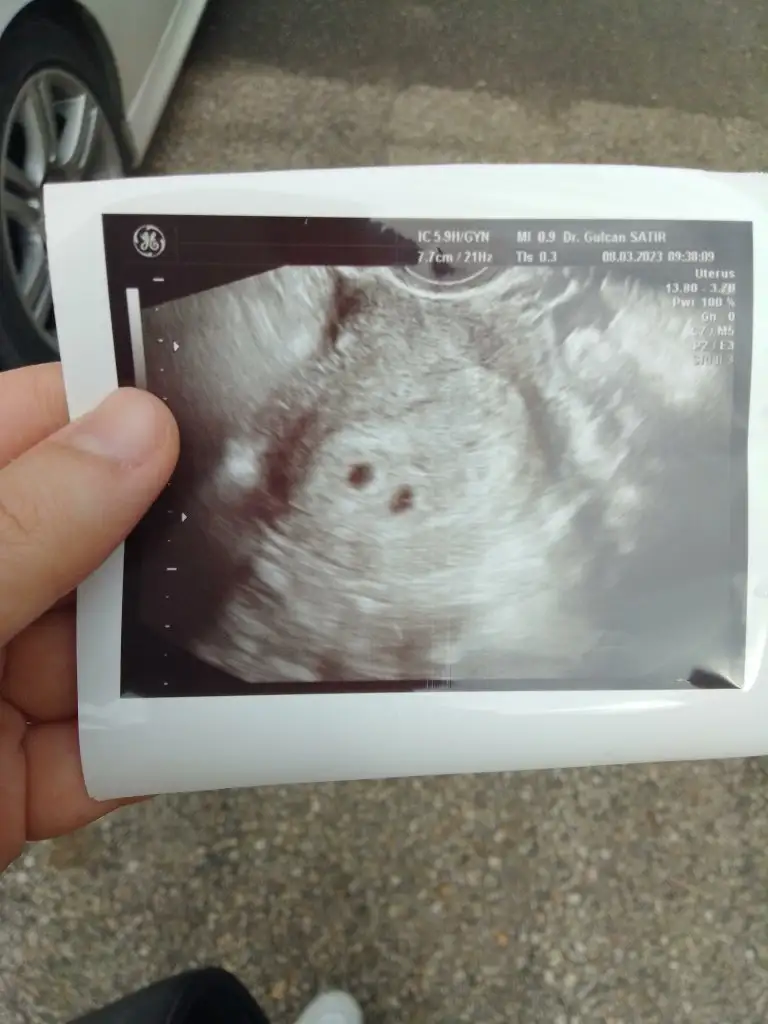

Canım 5+6 dayız dayanamadik eşimle özele gittik. Açıkçası birşey beklemeyi ummuyorduk daha küçük olduğu için gene sadece kese görünür diye düşünüyorduk. İlk önce karından ultrasonla baktı miniğim yeni oluşmuş kalp atışını duyduk pıt pıt🥰 sonra doktor kesenin hemen yakininda bir oluşum olduğunu düzgün goruntude olduğunu keseye benzettigini ama diğerinden kese boyutunun daha küçük ve icininde boş olduğunu söyledi. Sonrasında dediki bence ikiz gebelik olarak başlamış olabilir ama kesenin biri küçük içi boş ve kaybolacak muhtemelen bu tek gebelik dedi. Sonra çıkmadan önce vajinal ultrasonla da bakalım mi bebeğe zararı varmı kanama alanı da olabilir dedi bende tabiki bakalım dedim. Vajinal ultrasonda bir baktık ki digeride keseymis ve içi dolu orda da bebiş var ve çok şükür az da olsa ondan da kalp atışı duyduk😍 galiba bu ikiz meselesi biraz da his meselesi çünkü doktor böyle bişey görmemesine denemesine rağmen ben surekli böyle hissetmistim. Allah'ıma binlerce kez şükürler olsun inşallah sağ salim ikisinide kucağımıza almak nasip olur inşallah 🥰🤲🧿🧿🧿🧿🧿

Evet ikinci vajinal ultrasonda bile gene çok zorladı doktor bir türlü sabitleyemedi kalp atışını çok minik digerinden bir hafta kadar küçük ama uzun uğraş sonucu gördük çok şükür doktorda çok nazlı dedi😊Amin canım sağolasın inşallah ikisini de sağ salim kucağımıza alırız 🤲🙏🧿🧿🧿